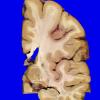

Neuronal Ceroid Lipofuscinosis (NCL) (11)